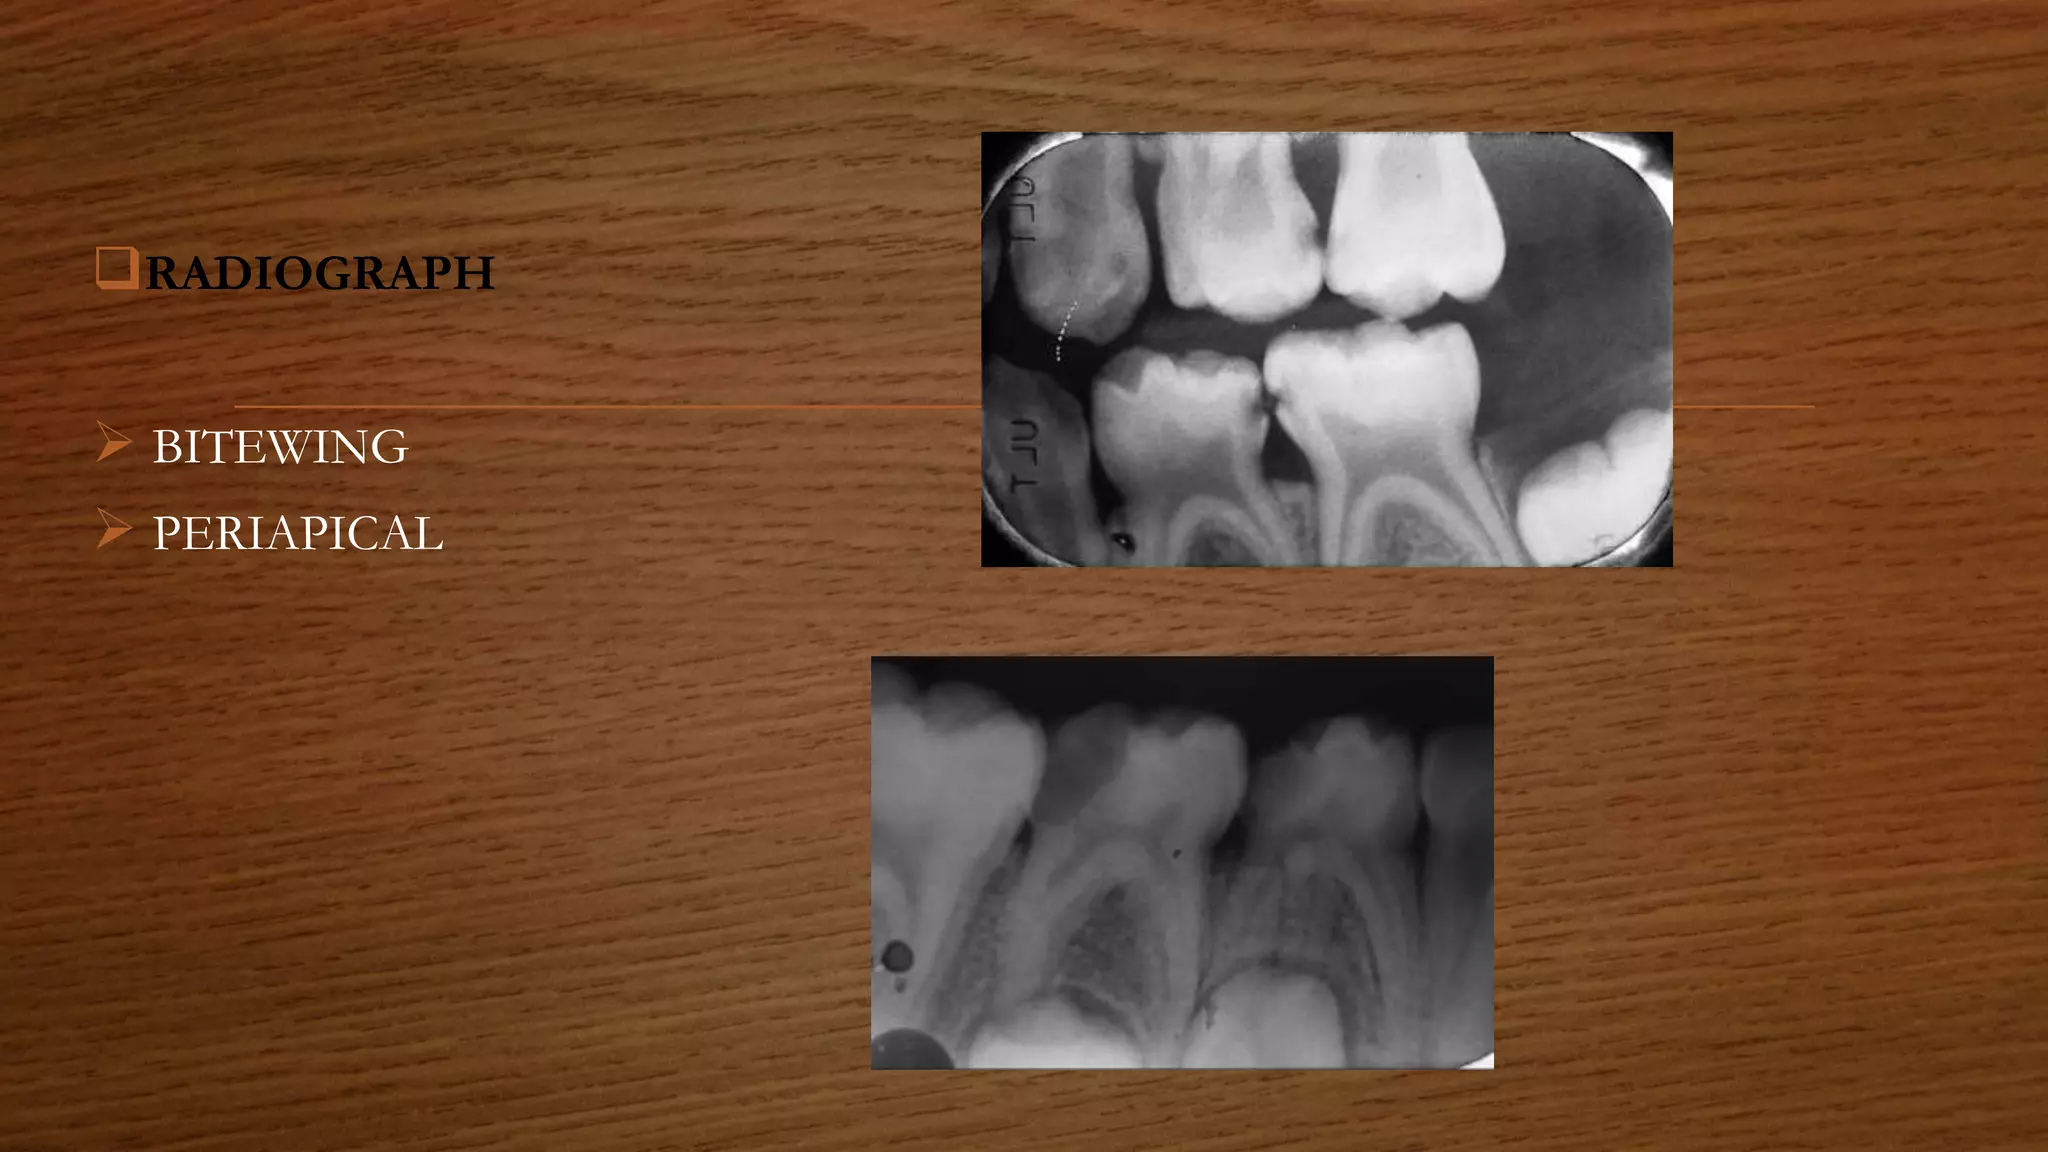

RADIOGRAPH

 BITEWING

 PERIAPICAL